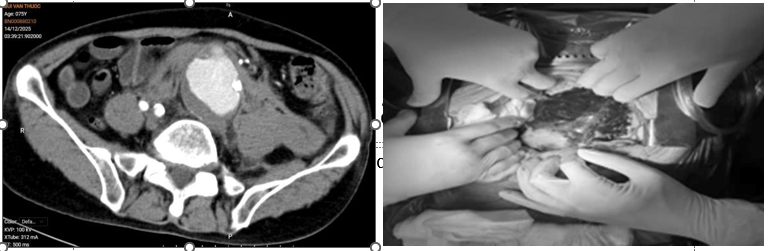

Người bệnh nam, 75 tuổi, nhập viện lúc nửa đêm trong tình trạng đau bụng dữ dội, huyết động không ổn định. Qua thăm khám lâm sàng và hình ảnh chụp cắt lớp vi tính (CLVT), các bác sĩ xác định người bệnh bị vỡ phình động mạch chủ bụng kèm khối máu tụ lớn trong ổ bụng, đe dọa trực tiếp đến tính mạng.

Hình ảnh khối máu tụ do vỡ động mạch chủ bụng trên phim chụp CLVT và sau khi mở bụng